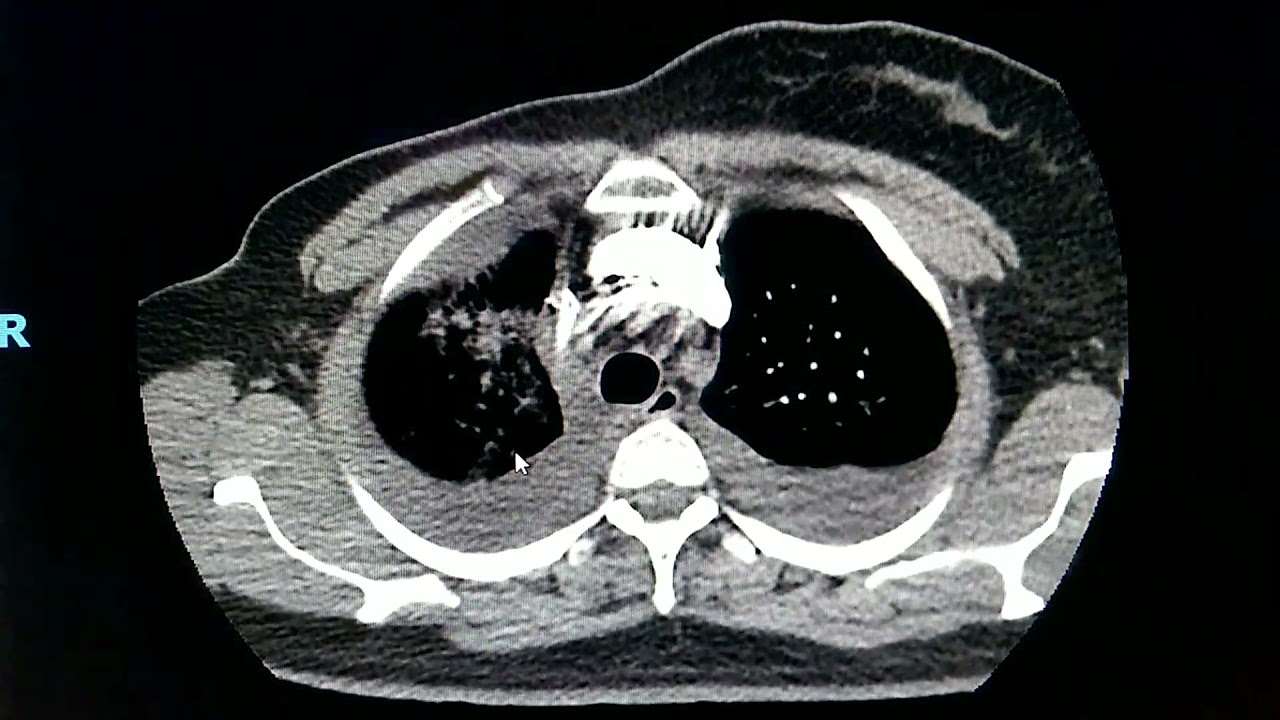

luzes uma luz verdadeira e uma luz falsa problema disso aí olha só a luz falsa maior a luz verdadeira menor Luiz falsa maior luz verdadeira menor o problema disso aí é que obviamente apre a fusão da Luz verdadeira é uma enquanto a do Luiz falsa é outra ou seja se eu tinha um vaso nobres saindo da Luz falsa a chance daquele órgão que é irrigado por esse vaso skinny a é muito alta então dissecção de aorta dica pode causar infarto quando disser pra coronária pode causar AVC quando de seca para carótida pode causar tamponamento cardíaco

quando rompe para o pericárdio então é um quadro um ponto inicialmente muito graves paciente precisa ser atingido com emergência digamos assim e não pode perder tempo tá tem que ir para hemodinâmica tem que ir para o centro cirúrgico e como é que eu sei se o vaso tá ou não saindo a luz verdadeira é muito fácil é só você conhecer o que que elas verdadeiro que que elas falsa a primeira dica pra isso eu já te dei à luz falsa geralmente é maior que a luz verdadeira mas tem outro sinal que eu vou te mostrar

agora aqui que é o seguinte ó a luz falso geralmente ela faz UnB Ah tá ela é mais aguda aqui ó e isso é chamado sinal do bico então Luiz falsa sinal do bico é maior geralmente do que a luz verdadeira e eu não quero ver isso daqui a gente esse colapso da Luz verdadeira como eu tô vendo aqui você que indica uma instabilidade o maior tal paciente pode ter aí mais estabilidade perfusional dos órgãos Ok beleza beleza então ó luz verdade verdadeira não Luiz falsa né grandona Luiz falso nos verdadeira que está em vermelho

pequenininho aqui isso aqui é um derrame pleural gente isso aqui não é derrame pleural no contexto de dissecção de aorta se não vai pensar que tem um derrame pleural ali de Bobeira isso aqui prova me encher um imo tórax provavelmente é sangue na cavidade pleural OK É isso aí Espero que você tenha gostado aula de hoje a gente se vê na próxima tchau